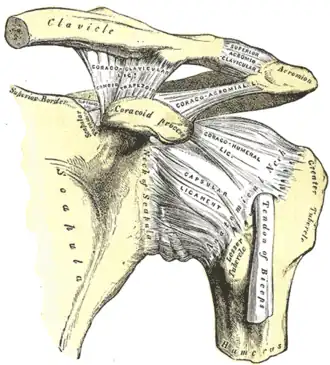

The left shoulder and acromioclavicular joints, and the proper ligaments of the scapula. Anterior view.

The left shoulder and acromioclavicular joints, and the proper ligaments of the scapula. Anterior view.